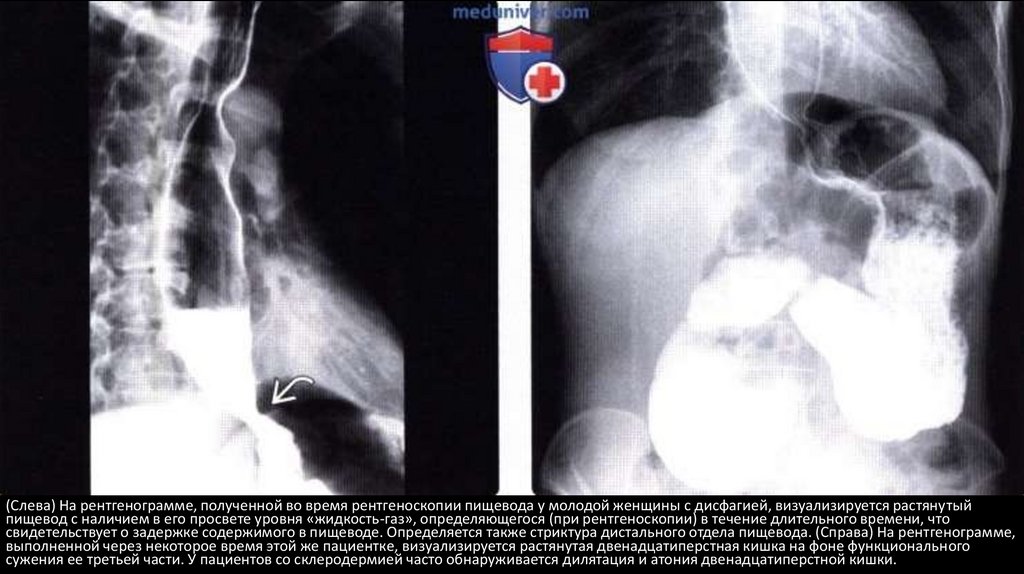

(Слева) На рентгенограмме, полученной во время рентгеноскопии пищевода у молодой женщины с дисфагией, визуализируется растянутый

пищевод с наличием в его просвете уровня «жидкость-газ», определяющегося (при рентгеноскопии) в течение длительного времени, что

свидетельствует о задержке содержимого в пищеводе. Определяется также стриктура дистального отдела пищевода. (Справа) На рентгенограмме,

выполненной через некоторое время этой же пациентке, визуализируется растянутая двенадцатиперстная кишка на фоне функционального

сужения ее третьей части. У пациентов со склеродермией часто обнаруживается дилятация и атония двенадцатиперстной кишки.